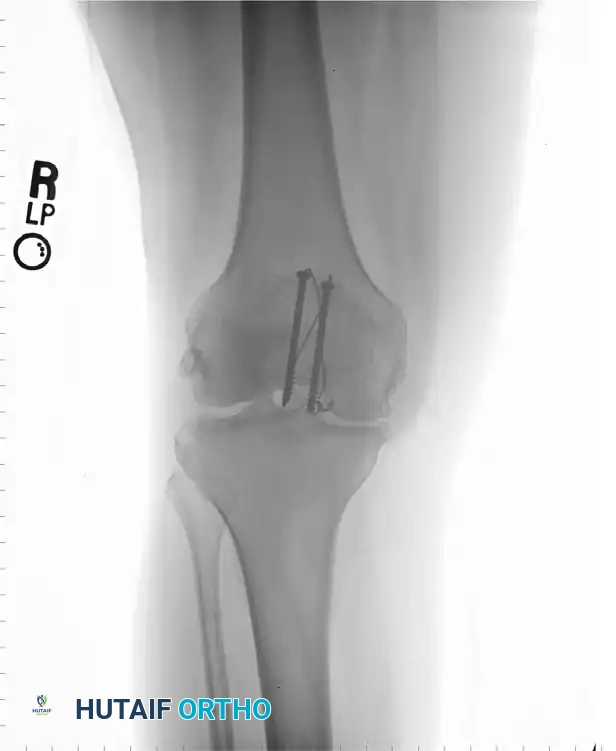

SURGICAL TECHNIQUE 54-21: STANDARD TENSION BAND WIRING

The following represents the definitive, step-by-step execution of the AO tension band wiring technique using Kirschner wires (K-wires).

3. Kirschner Wire Insertion

With the fracture anatomically reduced and held firmly with clamps, drill two 2.0-mm K-wires from inferior to superior through each fragment.

* Place these wires approximately 5 mm deep to the anterior surface of the patella.

* Position them along lines dividing the patella into medial, central, and lateral thirds.

* It is imperative to insert the wires as parallel as possible to facilitate uniform compression and prevent binding.

Schauwecker described a highly effective method of compression wiring using supplemental lag screws for comminuted fractures. The principle is to convert a multi-fragmentary fracture into a stable, bifragmental fracture before applying the tension band.

- Fragment Assembly: The comminuted fragments (usually at the inferior or superior pole) are anatomically reduced.

- Lag Screw Fixation: Mini-fragment lag screws (2.0 mm or 2.7 mm) are placed horizontally or obliquely to compress the comminuted fragments together. This effectively transforms the comminuted fracture into a simple transverse pattern.

- Tension Band Application: Once the fracture is bifragmental, a standard figure-of-eight tension band wire is applied over the anterior surface of the patella to neutralize the extensor forces.

Cannulated Screw Tension Band Construct

A modern, highly favored alternative to K-wires involves the use of 4.0-mm partially threaded cannulated screws. This technique offers superior biomechanical strength and significantly reduces the incidence of symptomatic hardware prominence.

Instead of driving K-wires, two 4.0-mm cannulated screws are placed longitudinally from inferior to superior across the reduced fracture. These screws provide independent interfragmentary compression. The 18-gauge tension band wire is then passed directly through the hollow cannulae of the screws, rather than around protruding K-wire ends.

This construct creates a highly stable, low-profile fixation. The screws compress the articular surface, while the wire through the screws acts as the anterior tension band, neutralizing the distracting forces of the quadriceps.